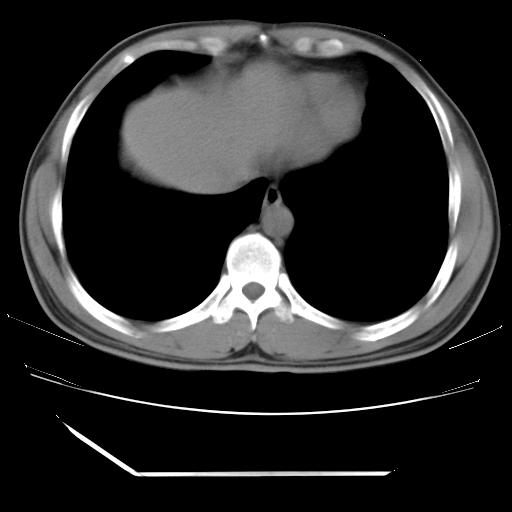

男,38岁,于2009年8月9日晚突发左侧胸痛,今x线提示左下肺阴影,为了明显确诊断,行ct检查,

血常规:嗜酸性细胞增高,单核细胞增高。

纵膈窗

病灶发生在下叶,密度均匀,边缘模糊、毛糙,周围血管纹理增强扭曲改变,靠近胸膜处病灶胸膜反应明显。

支持考虑---球形肺炎。

左肺舌叶病变。主体病灶呈类圆形中心密度低,成液化趋势周边班片影分布

考虑肺脓肿

虽然实验室检查支持炎性病变,且病变内有坏死改变(中央呈大片状低密度影),但仍不能掉以轻心,鳞癌也可以有这种影像改变。